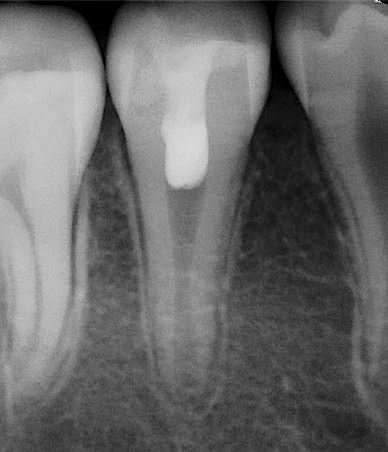

At the final regenerative endodontic treatment appointment, a 3% mepivacaine solution without a vasoconstrictor is used to obtain local anesthesia (the lack of a vasoconstrictor will allow for periapical bleeding). A rubber dam is placed, and after the tooth is accessed, 17% EDTA is used to irrigate the canal in conjunction with files to remove the calcium hydroxide and prepare the dentin. Next, the canal is dried, and bleeding is induced with a hand file 1 to 2 mm beyond the apical foramen. The blood should be stopped at a level in the canal (ie, cementoenamel junction) that will allow for the placement of 3 to 4 mm of restorative material (Figure 2). The induction of periapical bleeding into the canal space is necessary in regenerative endodontic procedures. The induced bleeding supplies scaffolding, stem cells, and blood-derived bioactive growth factors. These growth factors supplement the growth factors embedded in the dentinal matrix that are released when the 17% EDTA is irrigated into the canal.20-22 It has been shown that the stem cells from the apical papilla and the growth factors released from the dentin demonstrate an increased survival rate with the use of EDTA and calcium hydroxide.22 In contrast, the use of high concentrations of sodium hypochlorite and antibiotic paste have been shown to result in decreased stem cell and growth factor survival.23 The triad of stem cells, scaffolding, and growth factors is what enables the tissue regeneration to occur.24

(2.) The induction of canal bleeding after file insertion 1 to 2 mm beyond the apical foramen.

Figure 2